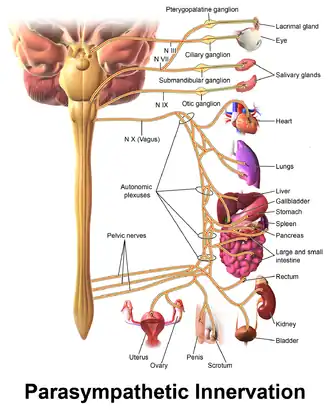

Adrenergic blocking agents are a class of drugs that exhibit its pharmacological action through inhibiting the action of the sympathetic nervous system (SNS)[1] in the body. The sympathetic nervous system is an autonomic nervous system that we cannot control by will. It triggers a series of responses after the body releases chemicals named noradrenaline (norepinephrine) and adrenaline (epinephrine).[1] These chemicals will act on adrenergic receptors, with subtypes alpha-1, alpha-2, beta-1, beta-2, and beta-3, which ultimately allow the body to trigger a fight-or-flight response to handle external stress.[1] These responses include vessel constriction in general vessels whereas there is vasodilation in vessels that supply skeletal muscles or in coronary vessels.[1] Additionally, heart rate and contractile force increases when the SNS is activated, which may be harmful to cardiac function as it increases metabolic demand.[1]

Adrenergic blocking agents treat certain diseases through blocking the adrenergic receptor,[2][3] preventing it from being activated by noradrenaline and adrenaline. As a result, it stops the body from producing the fight-or-flight response.